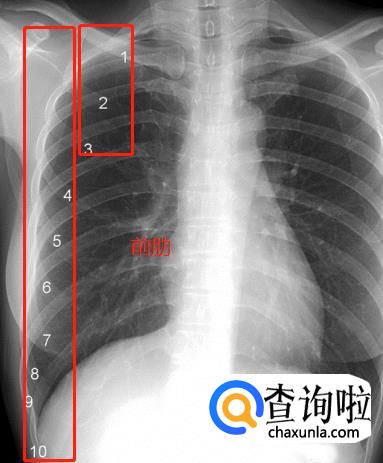

肋骨。一根肋骨在正位胸片上投影的前后端并不在同一水平,为了便于描述,肋骨被人为的分为后段(后肋)和前段(前肋)两个部分。后段通常是肋骨从胸椎到肺野外缘的投影,走行大致水平或略向外下倾斜。前段从肺野边缘起向内下呈比较大角度的斜向走行,越是接近第11、12肋的肋骨,其前段向下倾斜的角度越大。图中1~11分别标示第一到第十一后肋。